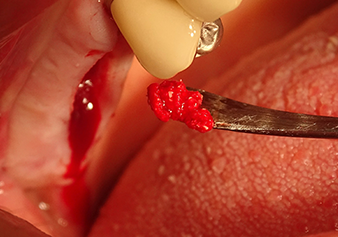

L’insert I2A (diamètre 2,0 mm) est ensuite utilisé pour perforer le plancher sinusien par intermittence et à la plus petite échelle possible. Cette méthode piézochirurgicale spéciale garantit que la membrane de Schneider n’est pas endommagée. Quand le Z25P est utilisé, la membrane est déjà légèrement relevée sous l’effet du fluide de refroidissement délivré via la pointe de l’insert (Fig. 3). Seulement 50 % du fluide de refroidissement sont éjectés afin d'éviter une pression élevée sur le site implantaire.